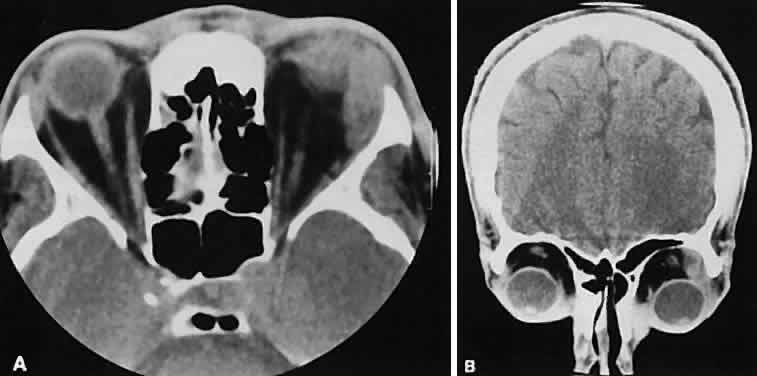

The muscle belly has a smooth contour with no edema of the adjacent orbital fat. We recently evaluated a patient with a referral diagnosis of Graves' orbitopathy. The patient was euthyroid but had severe orbital congestion typical of advanced Graves' orbitopathy. Imaging showed “dirty” orbital fat and lateral rectus muscle morphology that seemed atypical (Fig. 8). Biopsy specimen results showed a low-grade lymphoma. Hypertrophy of the medial rectus muscle can cause the medial wall to bow in toward the ethmoidal sinus from the chronic effects of pressure on the bone. The hypertrophied muscles also can give rise to a compressive optic neuropathy in the orbital apex as the enlarged muscles take their origin from the anulus of Zinn. Axial views of the apex show an apparent mass if the inferior rectus muscle is enlarged. It is imperative that additional views, sagittal or preferably coronal, be obtained to show the true nature of this apparent mass. Intracranial fat prolapse, seen by CT, may be another sign of optic neuropathy.44 An optic neuropathy also can be seen with relatively normal-sized EOM. An expanded fat compartment with optic nerve stretch has been associated with an optic neuropathy.45,46

Fig. 8. Low-grade lymphoma confined to orbit mistaken for Graves' ophthalmopathy in a 65-year-old man. A. On the axial view, orbital fat appears “dirty” with marked increase in soft tissue stranding. Muscles do not have a smooth appearance, lateral rectus muscles have lumpy appearance (arrow), and both lateral rectus muscles are disproportionately large for what typically is seen in Graves' orbitopathy. B. Coronal view also shows dirty orbital fat. Note left inferior rectus, which is small (arrowhead), and also is atypical in Graves' orbitopathy when there is enlargement of the other extraocular muscles.